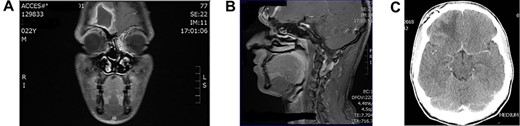

Case 4: frontal lobe abscess

Young man referred as a case of frontal lobe abscess as a complication of untreated frontal sinusitis. The patient presented with fever, headache and changes in personality and mood. Coronal MRI brain (Fig. 4A) showed a large frontal lobe abscess and an inflamed frontal sinusitis as in Fig. 4B. the patient was managed with a combination of intravenous antibiotics, endoscopic frontal drainage and frontal craniotomy to drain the frontal abscess by the neurosurgery team. Patient tolerated the procedures well with no complications as shown in postoperative CT brain (Fig. 4C).

(A) Preoperation coronal MRI brain with large frontal lobe abscess, (B) preoperation sagittal MRI of frontal lobe abscess extending from inflamed frontal sinus and (C) post drainage CT brain showing complete resolution of the frontal abscess.